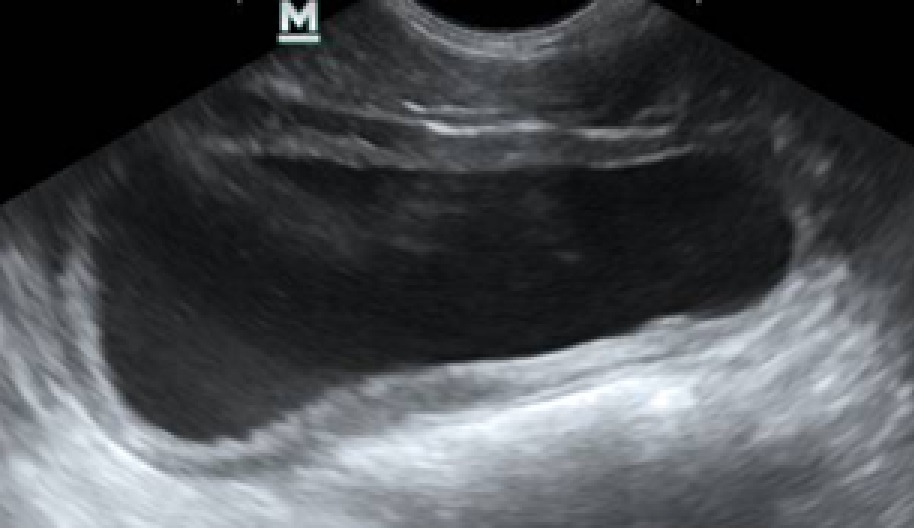

Ультразвуковое исследование (УЗИ). У животных с диагнозами «цистит» и «уроцистит» выявляли следующие изменения: мочевой пузырь лоцировался топографически правильно, имел овоидную форму. Его объем варьировался в зависимости от степени наполненности, при частичной обструкции мочеиспускательного канала объем остаточной мочи был увеличен. Содержимое пузыря анэхогенной природы, нередко с наличием мелкодисперсной взвеси различной эхогенности (рис. 3), стенка утолщена (рис. 4).